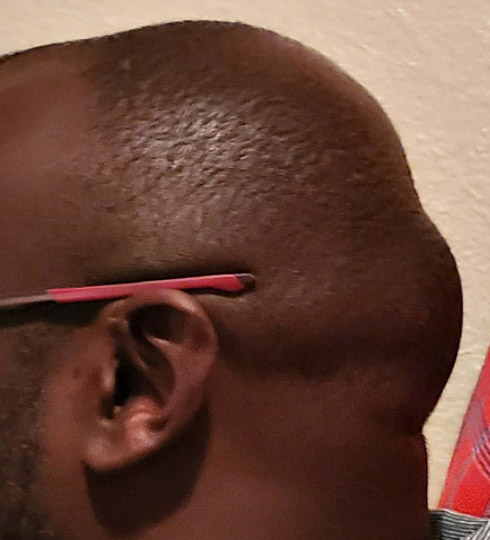

Desire for head shape asymmetry improvement as the final stage of total skull reshaping surgeries. (previous skull implants are in green color)

Placement of custom temporal implant through an incision behind the ear.

Desire for head shape asymmetry improvement as the final stage of total skull reshaping surgeries. (previous skull implants are in green color)

Placement of custom temporal implant through an incision behind the ear.